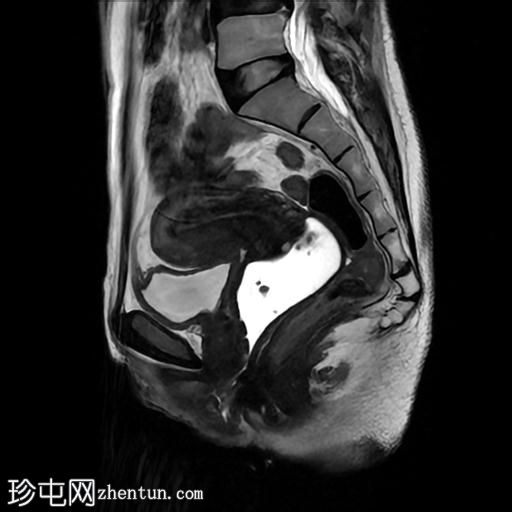

矢状位

T2加权像

该宫颈癌体积较大,局部晚期,大小为22 x 40 x 42 mm,起源于宫颈左后外侧壁,向下延伸至阴道上三分之一处,位于宫颈中后外侧壁。

病变还累及左侧前外侧的宫旁组织。

影像学检查结果提示,根据 FIGO 分期系统,该患者为宫颈癌 IIIC1 期。

宫颈肿块活检的组织病理学报告显示为宫颈鳞状细胞癌,具体来说是角化型。